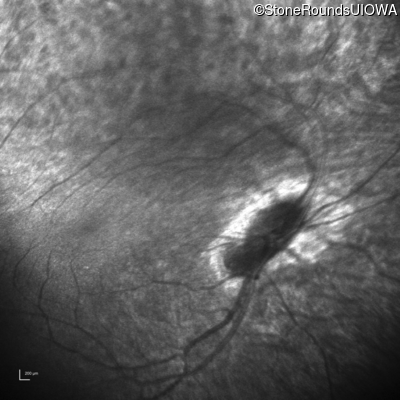

Infrared Fundus Photograph - Right - 1/700 sc

Exemplar